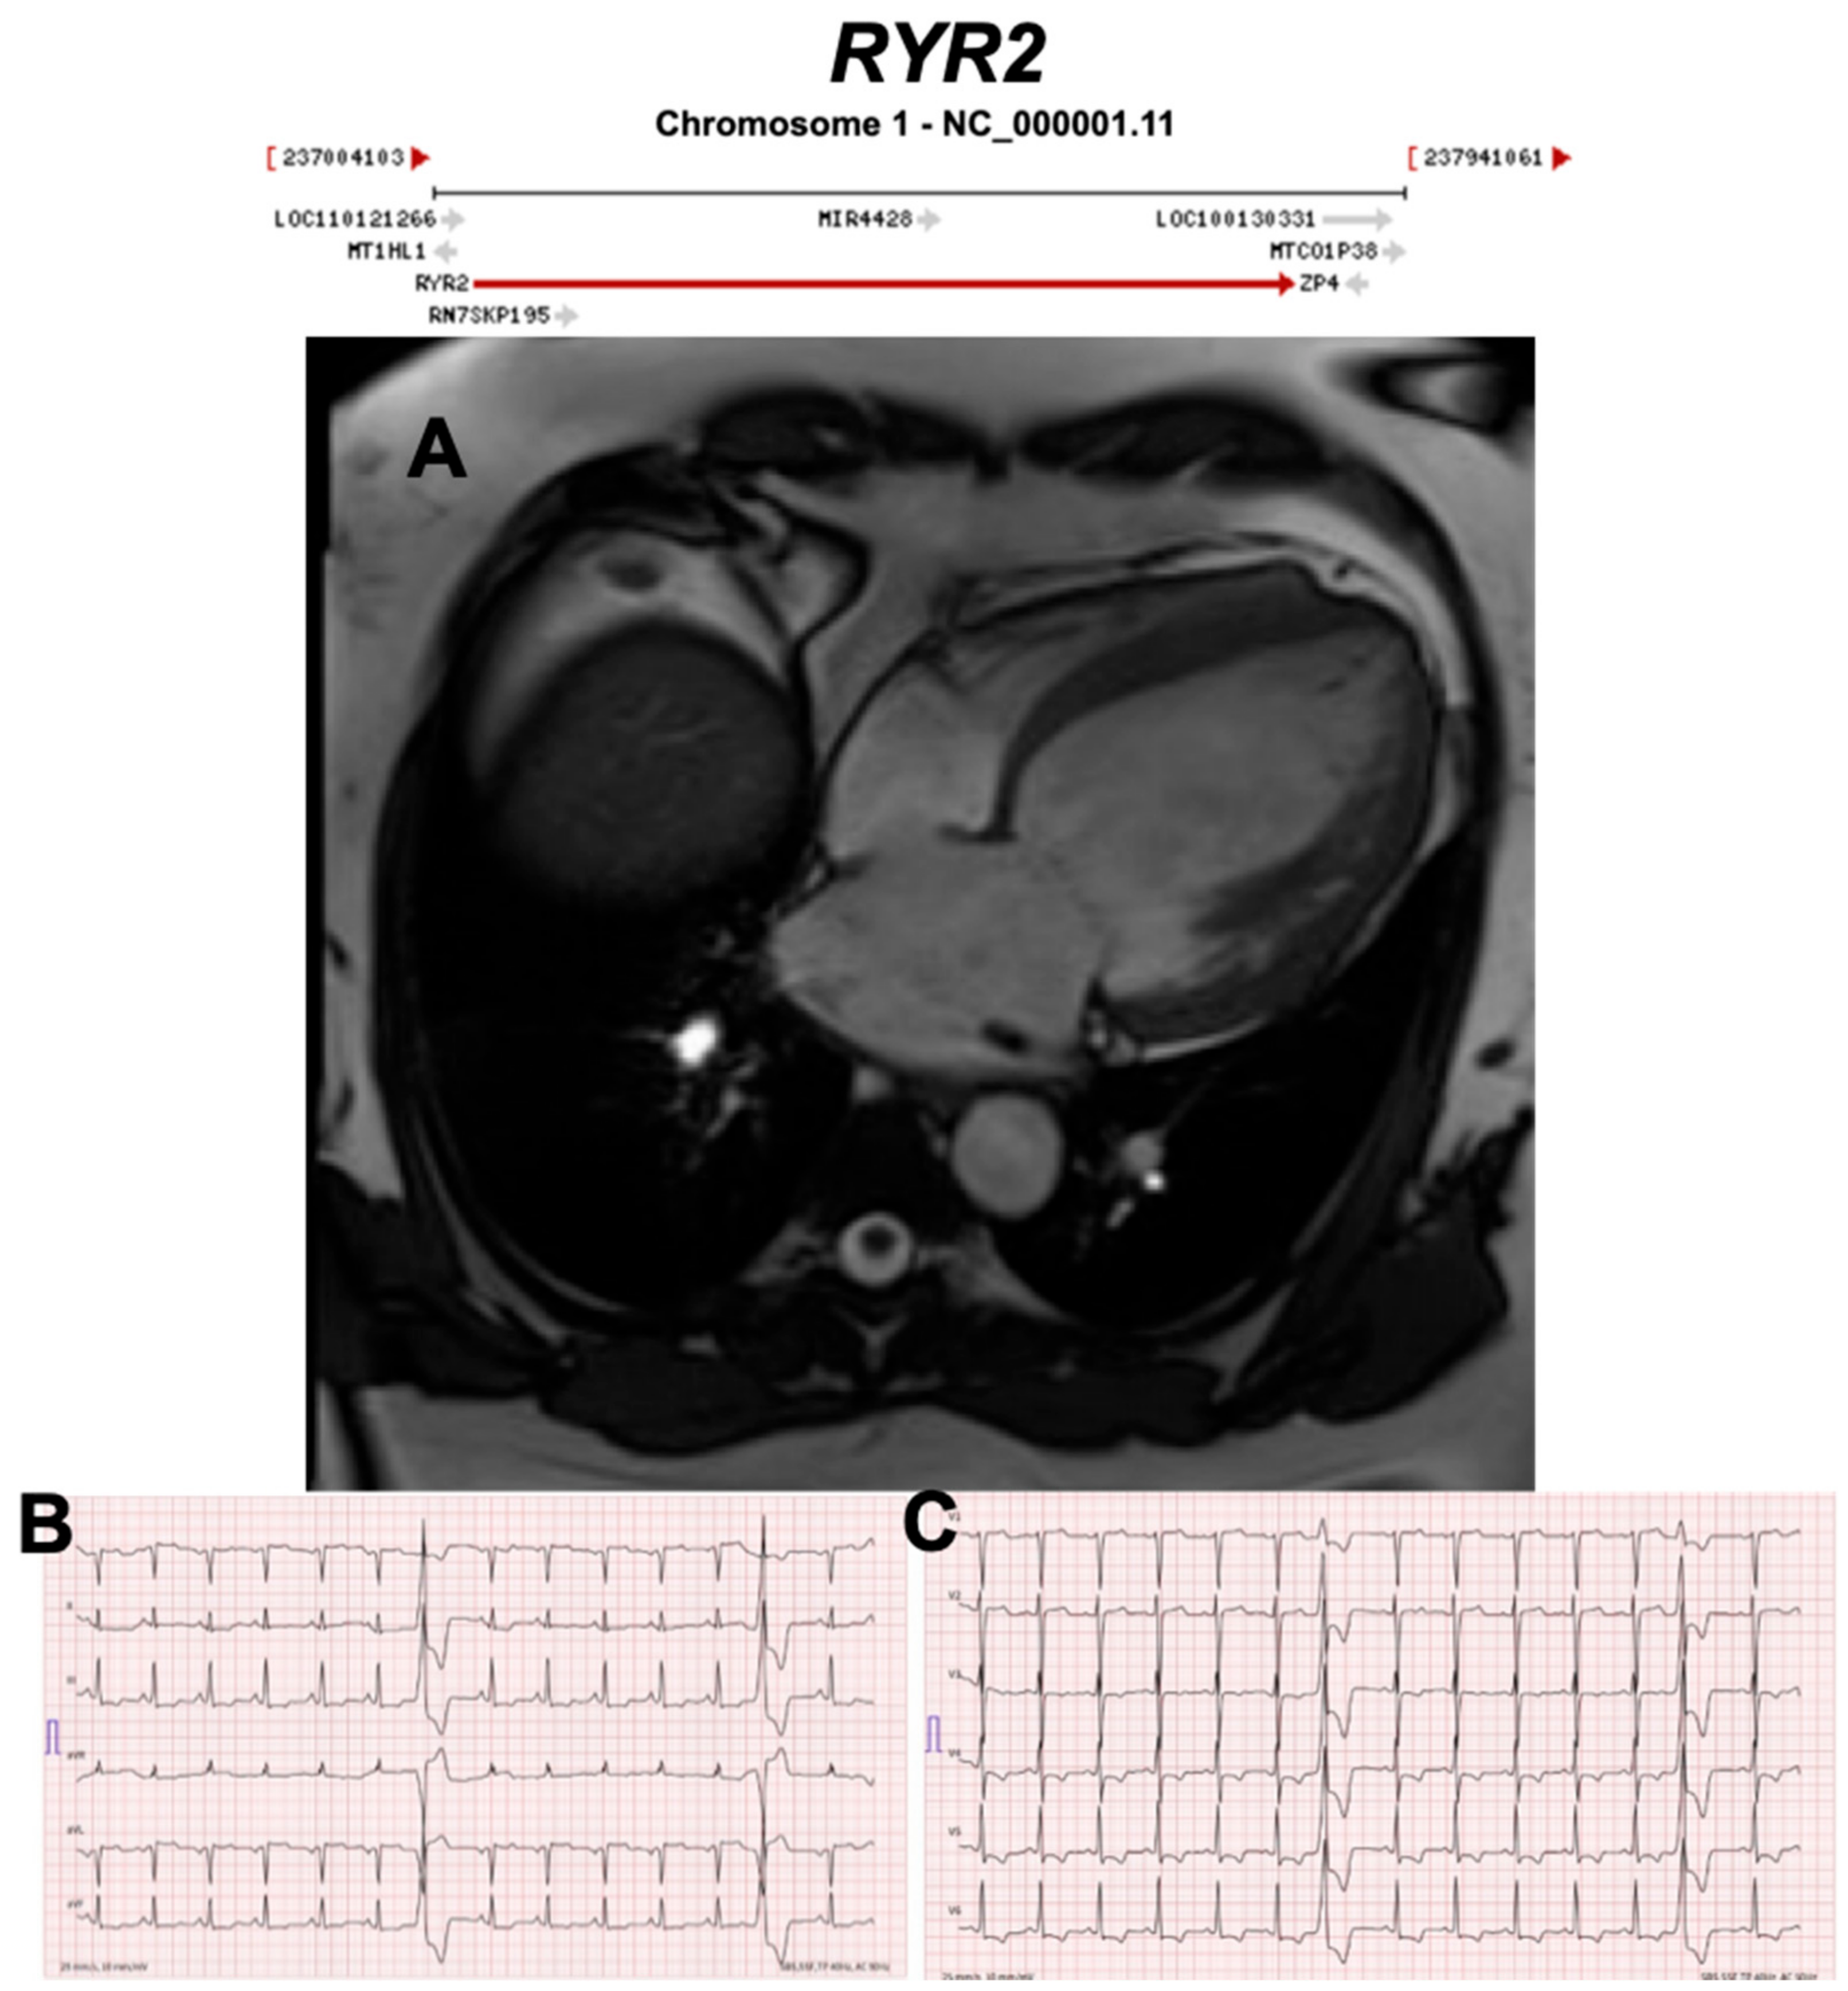

Figure 17.

Exemplar MRI and ECG finding found in ACM patients with RYR2 mutations. (A) CMR of a patient with RYR2 p.Trp98Ter mutation showing dilated cardiomyopathy; (B,C) 12-lead ECG showing inverted T waves in leads II, III, aVF, V3–V6, and two premature ventricular complexes originating from the anterobasal left ventricle. Reproduced with permission from Costa et al. (2020) [48].